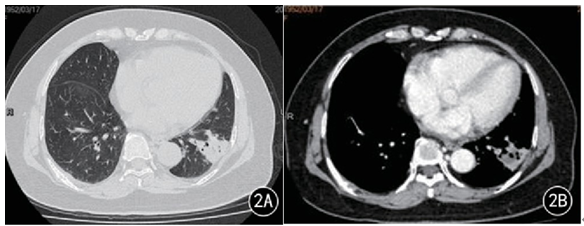

影像学特点

单发或多发的肺实变,常伴空洞。

底部贴近胸膜的楔形阴影。

单发或多发的小结节和晕征。

反晕征。

气管内病变。

其他:胸腔积液,累及纵隔、肋骨等。

图片

注:单发或多发的小结节和晕征

注:反晕征